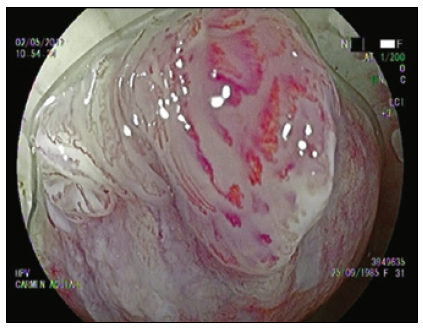

Cromoendoscopía digestiva magnificada en sustitución de la AAR convencional

La AAR en la literatura actual es sinónimo de colposcopía anal con tinción química.5, 7, 17, 18 Utilizando las nuevas tecnologías de la videoendoscopía digestiva es posible alcanzar una magnificación óptica de 200x, significativamente superior a la de un colposcopio de última generación. Nosotros trabajamos con una imagen magnificada de 100x que nos permite un mejor manejo del foco (Figuras 1 y 2).

El uso de capuchón es necesario al comienzo del entrenamiento. Con el advenimiento del sistema Laséreo, hemos sustituído la acetotinción por la cromotinción electrónica. Esto ha simplificado la técnica, acortando los plazos y las rotaciones del anoscopio, que pueden resultar molestas especialmente cuando hay hemorroides. El destaque de los cambios en el patrón vascular y glandular es igual de efectivo (Figura 3). El uso del colonoscopio permite valorar el recto, más allá del canal anal, con el fin de diagnosticar las metaplasias escamosas que pueden ser asiento de displasias VPH (Figura 4).